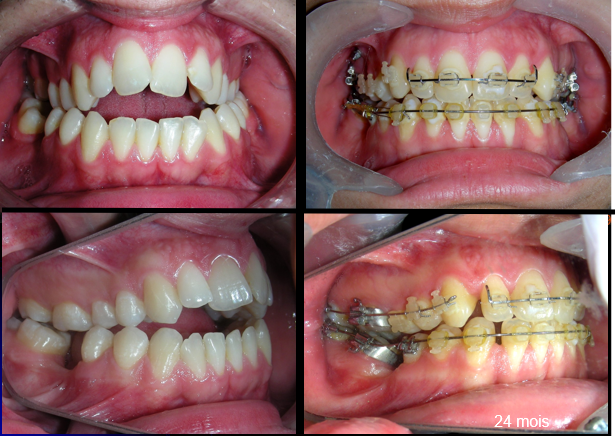

Extraoral clinical examination revealed a vertically long face with an increased lower facial third. The facial profile was slightly convex, with poor chin projection. Intraoral examination showed an AOB and bilateral posterior crossbite.

The patient presented with an anterior open bite, characterized by the absence of vertical overlap between the upper and lower incisors, and bilateral posterior crossbite. Extraoral examination revealed a vertically long facial pattern with an increased lower third of the face. The profile is convex with a retruded chin, indicating sagittal and vertical skeletal imbalances. We find also the inclined bipupillary line, which corresponds to facial asymmetries and altered occlusal plane.

Absent #16, #36 and #46 , No Angle molar relationship . Projection of canines axes in class II relationship . Anterior open bite: Over Bite – 8 mm). Bilateral posterior crossbite: Involvement of upper posterior sectors with inverted buccal-lingual relationship. Moderate Crowding at the level of the upper and lower incisors. Acceptable Oral Hygiene with no periodontal issues

After two years of treatment using appropriate biomechanics, the overbite was successfully corrected from -8 mm to +1 mm, achieving complete closure of the anterior open bite without exacerbating the patient’s lower facial third vertical proportions. At this stage, occlusal contacts were verified using articulating paper, and functional movements of the canines and incisors were evaluated to ensure proper anterior guidance and disclusion patterns. The patient was then referred to speech therapy (myofunctional evaluation) as part of the pre-debond assessment protocol.